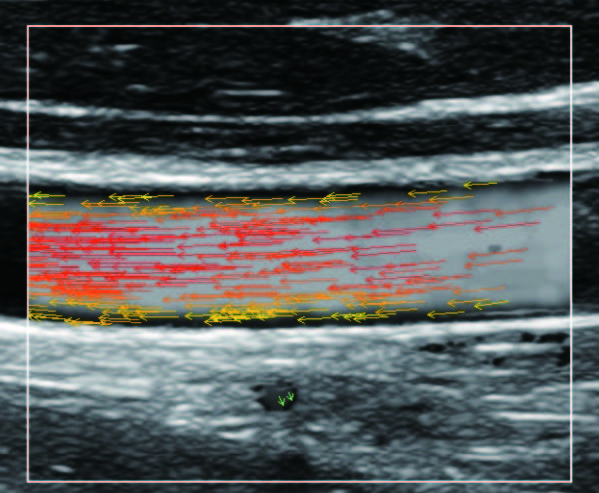

Метод визуализации интуитивно понятен и состоит из массива цветных стрелок, которые демонстрируют скорость и направление движения частиц крови.

На изображениях, приведенных ниже показаны примеры из клинической практики врачей ультразвуковой диагностики, полученные в процессе апробирования прибора Mindray Resona 7. Приводится наглядные примеры сравнения традиционного режима ЦДК и режима V Flow (Vector Flow).

Изображен ламинарный поток сонной артерии. В режиме ЦДК отсутствует информация о профиле ламинарного потока. Режим V Flow визуализирует не только скоростные характеристики с помощью цветных стрелок, но и предоставляет данные о профиле ламинарного потока (быстрый поток в центре и медленный вблизи стенок сосуда).